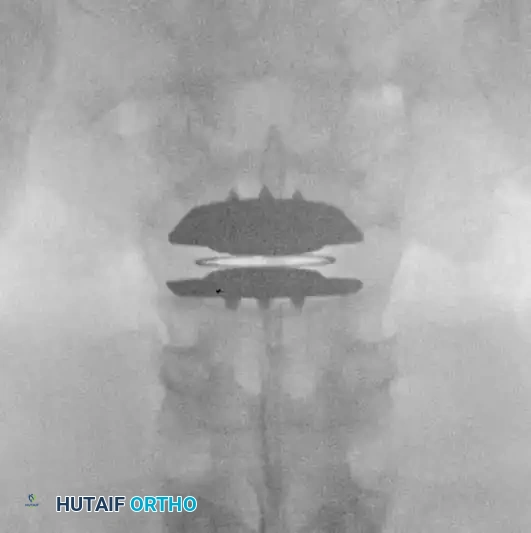

Fig. 39-47 A and B, Anteroposterior and lateral views of a patient with internal disc derangement treated with Charité total disc replacement.

The Charité Total Disc Replacement (TDR) represents a historical milestone in this biomechanical approach. It consists of two metallic endplates (typically cobalt-chromium-molybdenum) and a mobile ultra-high-molecular-weight polyethylene (UHMWPE) sliding core.